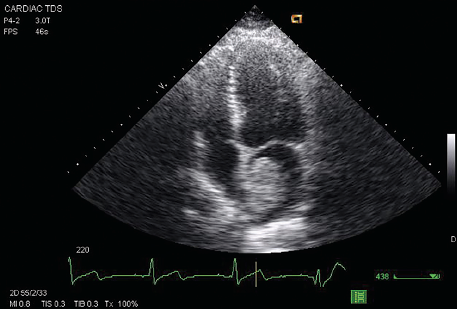

Preeclampsia

11/19/2014

Carlito Arenas, Jr., MD; Vincent Bryan Salvador, MD; Sabaa Joad, MD; Arunakumari Penumadu, MD; Valeriy Vilensky, MD

A 25-year-old African American, G2P2, without prior known comorbidities presented to the emergency department with 2 episodes of seizures, 8 days after an uncomplicated full-term normal spontaneous vaginal...